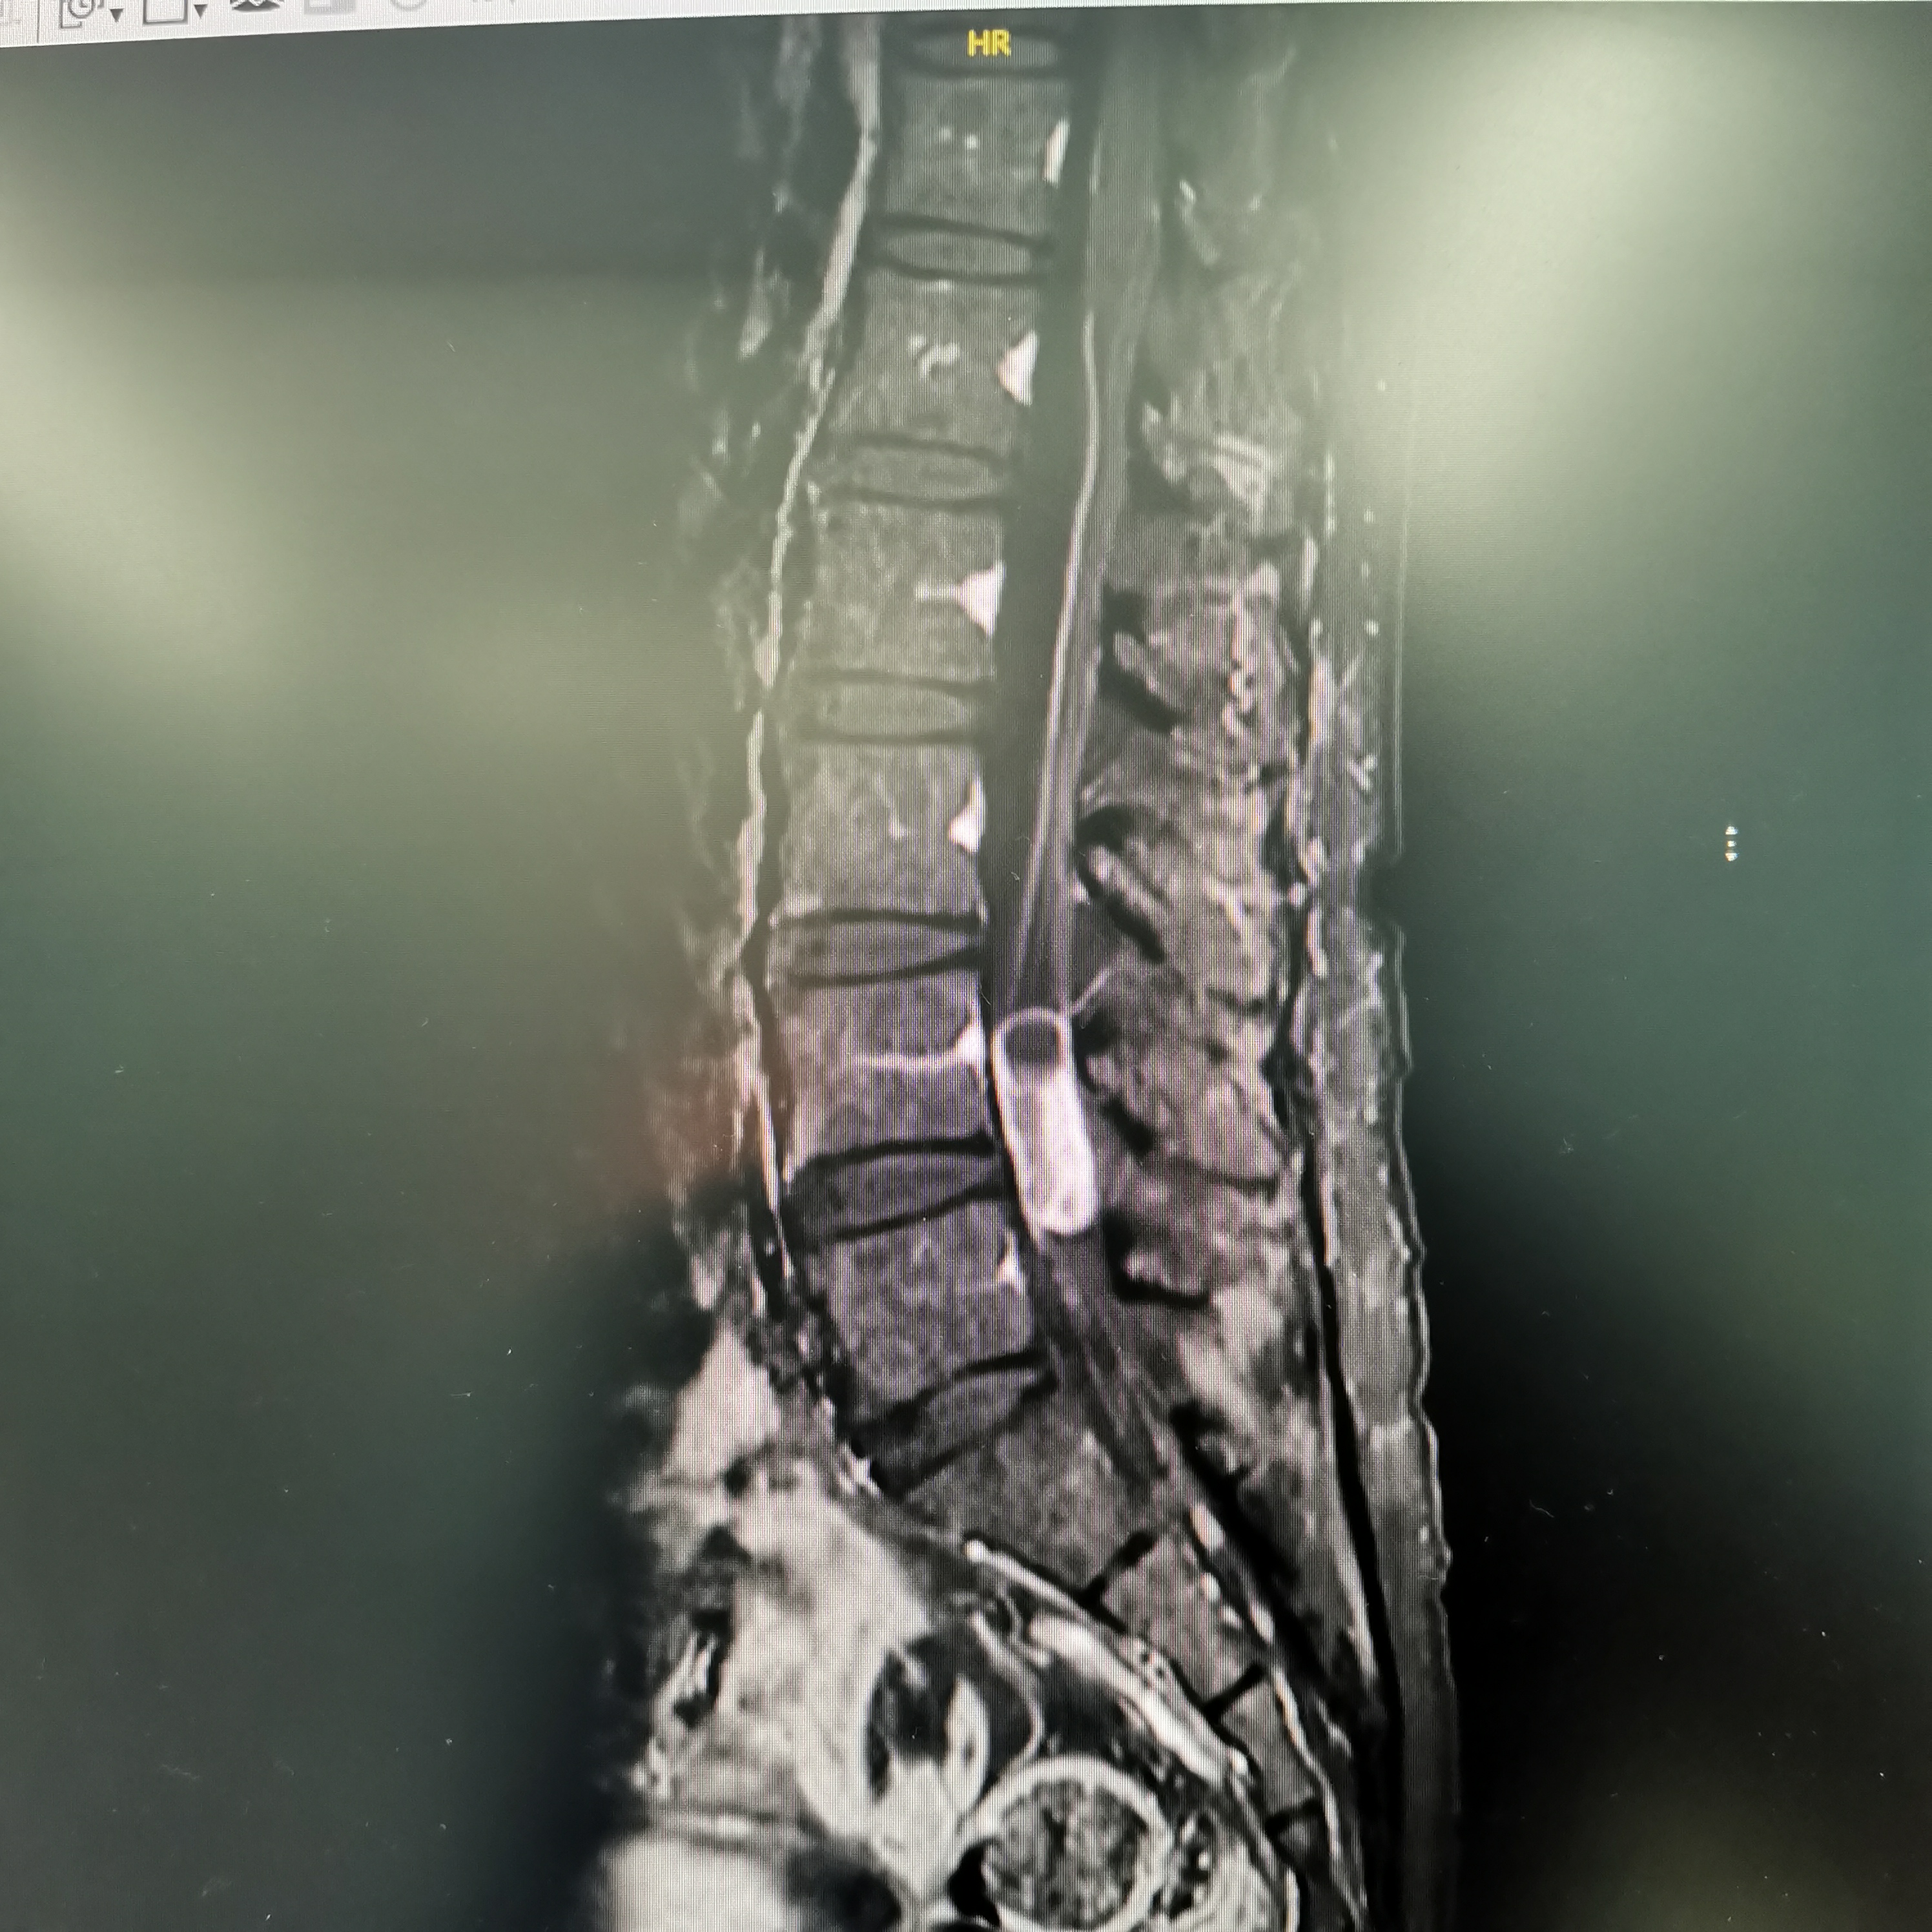

膝关节疼痛,原因是椎管内肿瘤,哑铃型生长,全切肿瘤,保留神经,疼痛症状消失…